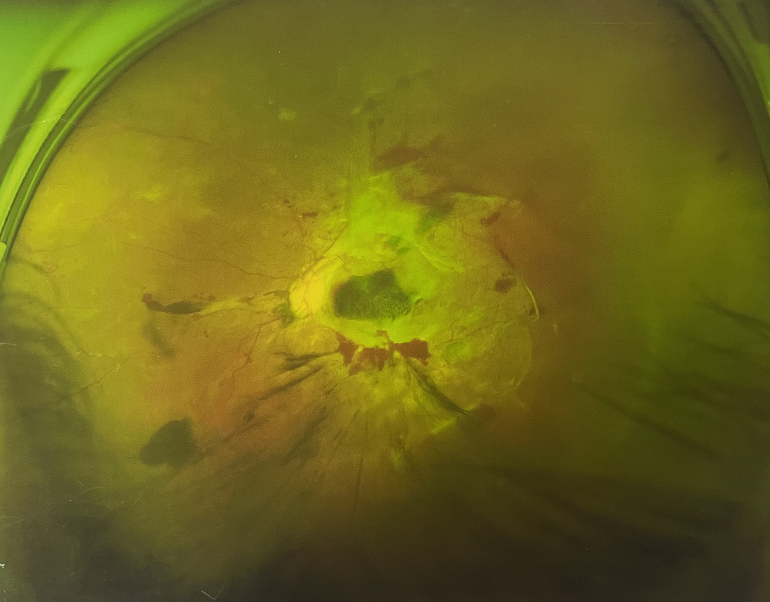

眼底出血一般多久能好?眼底出血可以由眼科本身疾病引起,常見的是視網(wǎng)膜靜脈阻塞、糖尿病視網(wǎng)膜病變、中心性滲出性視網(wǎng)膜病變、視網(wǎng)膜動(dòng)脈硬化、老年性黃斑病變、視網(wǎng)膜靜脈周圍炎。

另外,眼底出血還可以由全身疾病引起,比如糖尿病可以引起眼底出血,高血壓也會(huì)引起眼底出血,還有嚴(yán)重的腎病,血液方面的疾病都可以導(dǎo)致眼底出血。

眼底出血一般多久能好?眼底出血如果是輕癥,時(shí)間較短的患者大約3-6個(gè)月可以恢復(fù),如果是重癥或者病程較長(zhǎng)的患者,可能要持續(xù)1年,甚至2年時(shí)間。

眼底出血一般多久能好?眼底出血是醫(yī)生用檢眼鏡才能看到,患者和其他人看不見。眼底出血不是單獨(dú)的病,一般來說是由眼科本身疾病造成,還可以由全身疾病造成。比如常見的視網(wǎng)膜靜脈阻塞、糖尿病視網(wǎng)膜病變等引起的眼底出血較常見。眼底出血一般多久能好?所以眼底出血的出血吸收時(shí)間也不一樣,要根據(jù)病情輕重決定其預(yù)后,出血吸收時(shí)間也不一樣。